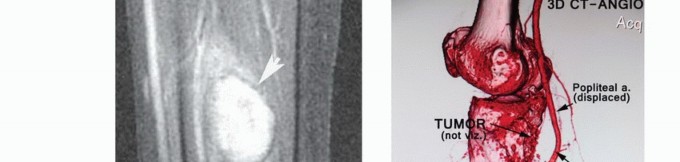

تصوير الأوعية ودراسات أخرى

يُعد تصوير الأوعية ثنائي المستوى مفيدًا جدًا في تحديد إزاحة الأوعية الدموية أو تغليفها بالورم. التحليل الدقيق لتشعب الأوعية المأبضية ضروري قبل الجراحة وقد يشير إلى تورط الورم وبالتالي الحاجة إلى البتر.